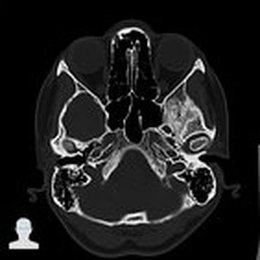

Anatomische Diagnostik - Computertomographie

Die Computertomographie (CT) ist eine weiterentwickelte Form der Röntgentomographie, bei der die durch Röntgenstrahlung erzeugten Informationen mittels eines Computers in errechnete Schnittbilder umgewandelt werden.

Schädel-CT V.a. bei Apoplexia cerebri (Schlaganfall), Blutungen oder Frakturen im Schädelbereich:

Differenzierung von Epi-, Subdural- und Subarachnoidalblutungen

Unterscheidung ischämischer und hämorrhagischer Schlaganfall

Nasennebenhöhlen-CT Bei einer Vielzahl von Fragestellungen der Hals-Nasen-Ohrenheilkunde, Beurteilung des knöchernen Labyrinthes.

Prinzipiell werden im CT das Knochenfenster und das Weichteilfenster unterschieden. Ein weiteres Fenster, das häufig Verwendung findet, ist das Lungenfenster. Im Knochenfenster – wie das Begriff bereits andeutet – sind vor allem knöcherne Strukturen gut beurteilbar. Im Weichteilfenster lassen sich vornehmlich parenchymatöse Organe und Muskeln relativ gut darstellen.

Für die Darstellung der Nasennebenhöhlen ist die CT Goldstandard, ebenso für den Bereich des knöchernen Labyrinthes. Für letzteres kann jedoch auch die MRT verwendet werden.